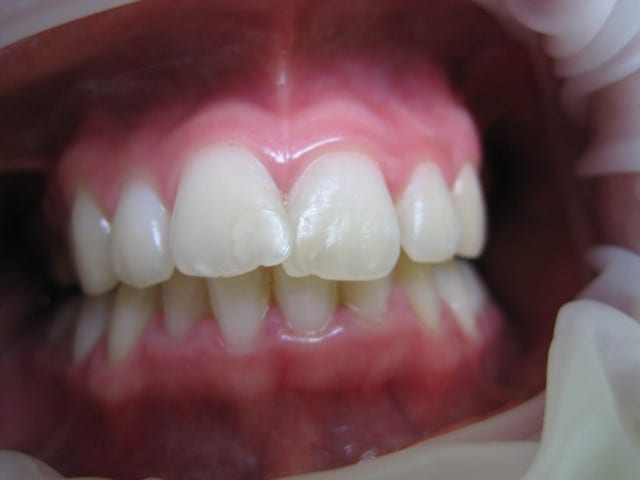

J'ai une patiente de 14 ans qui présente une full classe II due à un maxillaire en proposition car sur une base du crâne trop longue en antérieur. Le maxillaire a une longueur normale.

Voici les photos, radios et moulages du cas